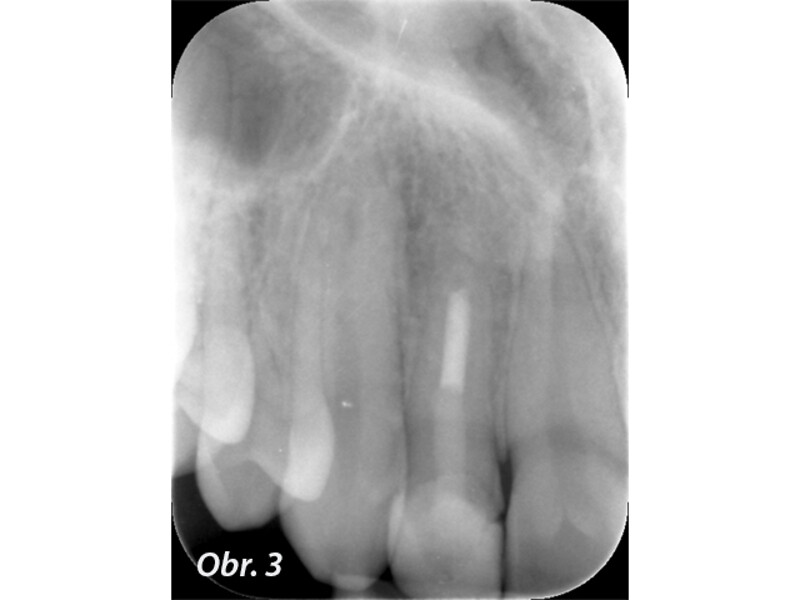

Indikační šíře MTA: Soubor kazuistik